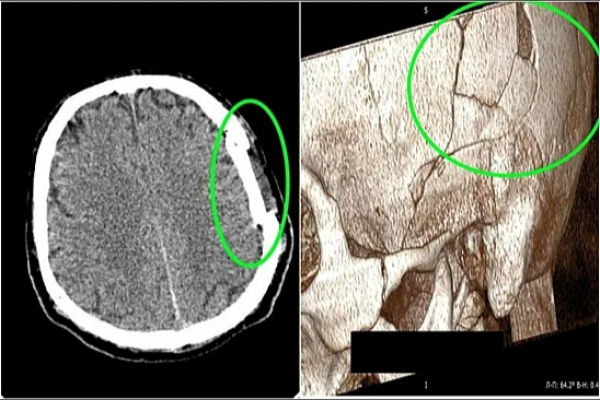

Диагностическое исследование с помощью рентгенографии и компьютерной томографии показало не только переломы костей черепа, но и сильное сдавление головного мозга, что могло привести к серьезным осложнениям, вплоть до необратимой потери функций центральной нервной системы. Благодаря слаженной работе нейрохирургов была проведена успешная операция, в ходе которой удалось восстановить анатомическую целостность черепа без использования имплантов и дополнительных внешних вставок.